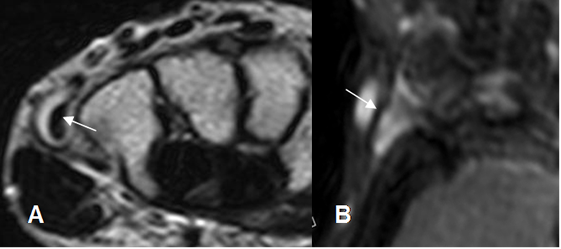

Fig 92. Tenosinovitis.

A: RM axial en T2 y B: RM coronal en STIR. Tendón del flexor radial del carpo rodeado por líquido, secundario a tenosinovitis.

Fig 93. Tenosinovitis.

A: RM axial en T2 y B: RM coronal en STIR. Tendón del extensor ulnar del carpo rodeado por líquido, secundario a tenosinovitis.